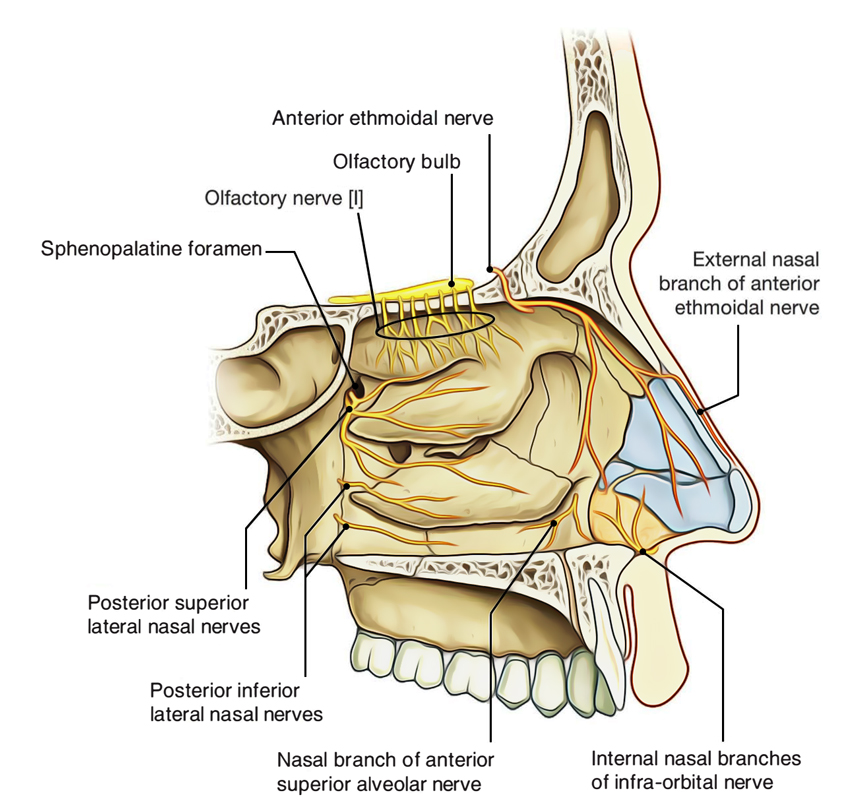

The lateral nasal wall consists of inferior and middle turbinates and occasionally a superior or supreme turbinate bone. The turbinates consist of three ridges of thin shell like bone known as the nasal conchae. The nasal passages are lined with a membrane composed primarily of one layer of flat closely packed cells called epithelial cells.

In bones behind your nose are your sphenoid sinuses. Anatomy of the nasal cavity. This region is divided into a labyrinth of slit like passages by multiple bony proturbances that fill the nose and act as shelves.

Internally the nasal septum divides the nasal cavity into a right and left side. They connect to your nasal passages in a complex network of air flow and drainage passages. One of the functions of the nose is to drain a variety.

The external nose consists of paired nasal bones and upper and lower lateral cartilages. The nasal cavity refers to the interior of the nose. The nasal cavity is the most superior part of the respiratory tract.